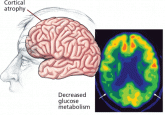

ArticleAlzheimer disease: Time to improve its diagnosis and treatmentAuthor:Stephen Correia, PhDPublish date: January 1, 2009Basic research is bringing a much-needed infusion of optimism and urgency to the clinical diagnosis and treatment of Alzheimer disease. Some of its...Read More